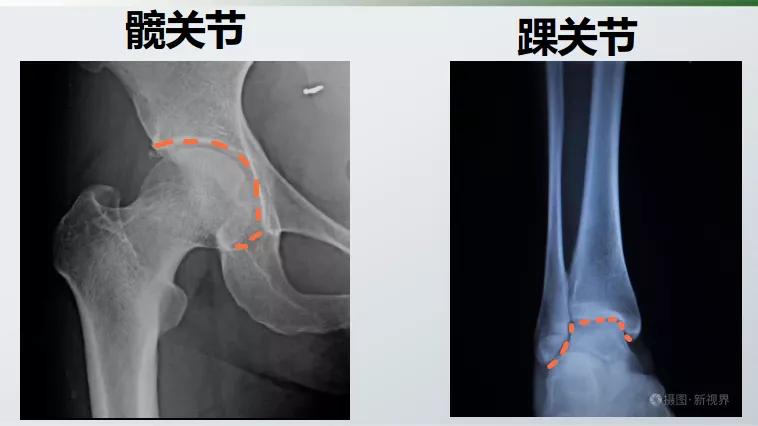

可是,下肢负重最大的应该是踝关节啊

髋关节承受髋以上的体重

膝关节承受膝以上的体重

踝关节几乎承受全身的体重

为什么最容易发生膝关节炎呢?

髋关节和踝关节都是半包围结构

相互嵌合,其骨头的稳定性好